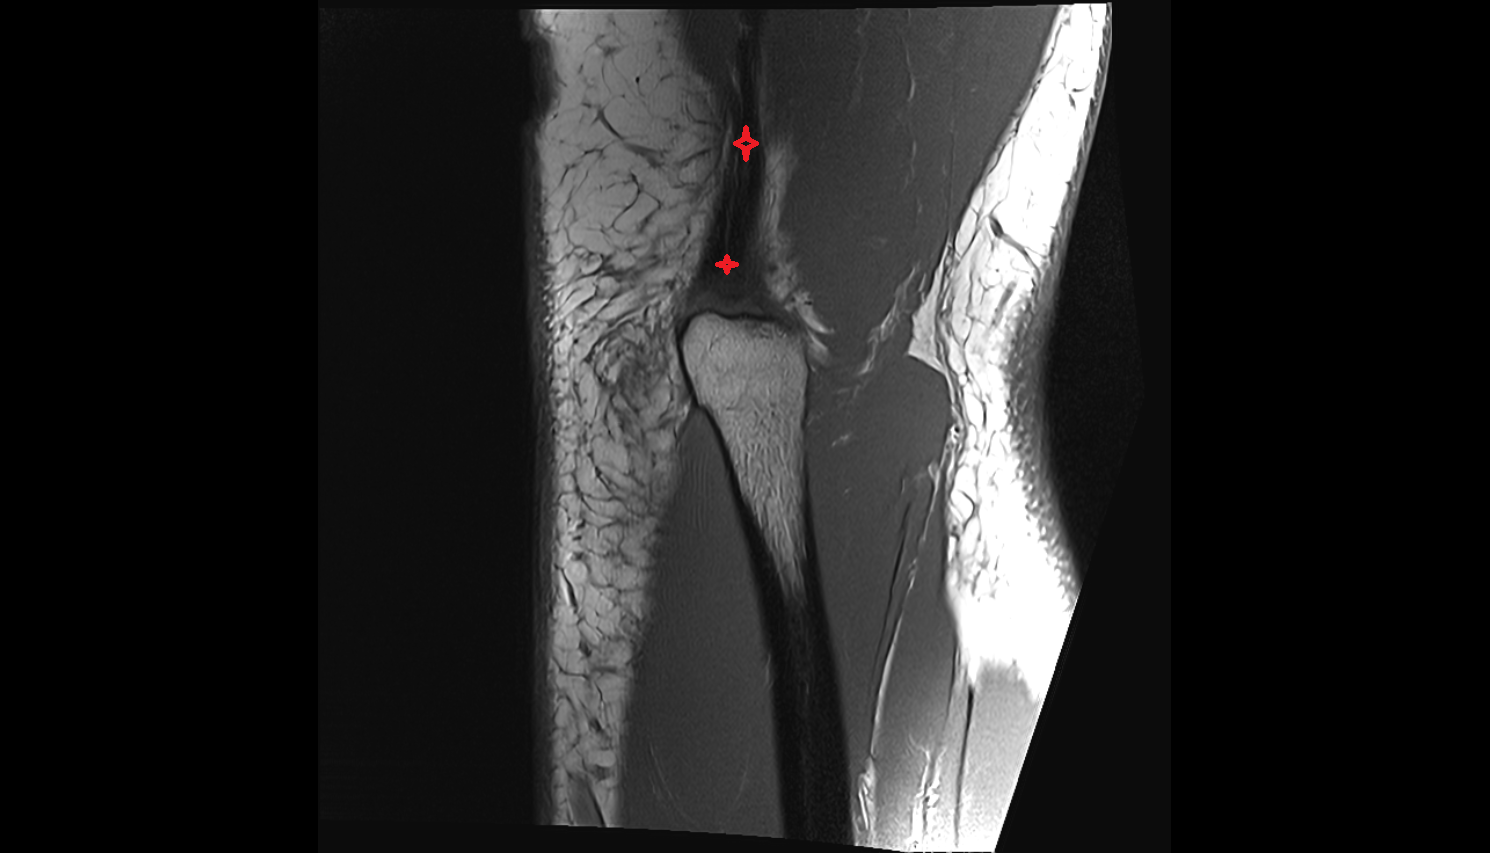

- Medial collateral ligament

- Lateral collateral ligament